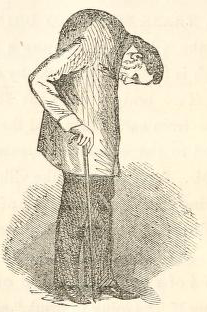

질병이 진행됨에 따라 척추의 운동성 상실과 흉부 팽창이 나타나며, 허리 굽힘, 측면 굽힘 및 신전이 제한된다. 체중 감소, 발열 또는 피로와 같은 전신 증상이 흔하게 나타난다.[55] 통증은 휴식 시에는 종종 심하지만 신체 활동을 하면 호전될 수 있다. 염증과 통증은 휴식과 움직임에 관계없이 다양한 정도로 재발할 수 있다.

골다공증은 강직성 척추염 환자에게 흔하며, 만성적인 전신 염증과 운동 능력 감소가 원인이다. 장기간에 걸쳐 척추의 골감소증 또는 골다공증이 발생하여 압박 골절과 등의 "혹"을 유발할 수 있다.[46] 척추 후만증은 이동성과 균형 장애를 유발하고, 주변 시야를 손상시켜 낙상 위험을 증가시킨다.[46] 진행된 강직성 척추염의 전형적인 징후는 X-레이에서 신데스모파이트 형성 및 골극과 유사한 비정상적인 뼈 성장이다. 척추 압박 골절에서는 신경 주변 조직 염증으로 인해 감각 이상이 나타나기도 한다.

척추 전체가 굳어 뻣뻣해지면 구부정한 자세가 되기 쉬운데, 이는 걸음걸이에 영향을 줄 수 있다. 척추 후만증이 심해지면 질량 중심(COM)이 앞쪽, 아래쪽으로 쏠리게 된다. 이렇게 무게 중심이 이동하면 무릎이 굽혀지고 발목이 위로 젖혀지는 식으로 보상 작용이 나타난다. 강직성 척추염 환자는 걸을 때 충격 흡수가 잘 안 되고 시야가 좁아져 조심스럽게 걷는 경향이 있다.[54]7. 역학